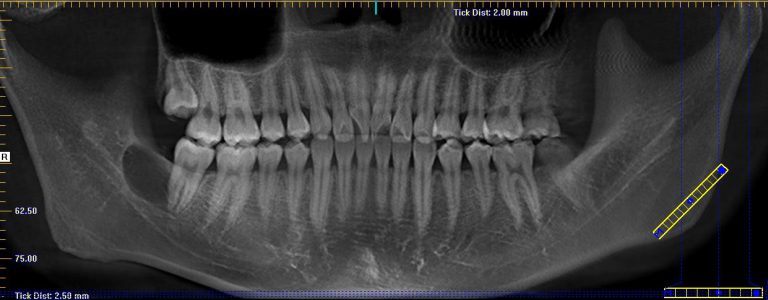

A 20-year-old male presented to our facility with a referral for a painful radiolucency of the right posterior mandible. Other than a two-year history of tobacco use, his past medical and surgical histories were unremarkable. On clinical exam, there were no mucosal changes, no palpable buccal or lingual swelling, and tooth #29, #30, #31 tested vital with no mobility, probing depths distal to #31 measured 7-8mm. On CBCT examination, the lesion exhibited a well-circumscribed, regular bordered radiolucency approximately 25mmx18mm in its greatest dimension in the right posterior mandible directly adjacent to #31. The lingual cortical plate was violated, however, the roots of tooth #31 remained intact. Additionally, the inferior pole of the lesion was contiguous with the superior aspect of the Inferior Alveolar nerve canal, but did not displace the nerve/canal (Figure 1). Tooth #32 was missing and, per patient report, had never developed. Differential diagnosis based on location and demographics included Dentigerous Cyst, Odontogenic Keratocyst, Ameloblastoma, Myxoma and Hemangioma in order of most to least likely diagnosis. After the risks, benefits and alternatives were discussed with the patient, he elected to undergo excisional biopsy under IV General Anesthesia.

A 19-year-old female presented with a one-week history of pain and swelling in the right mandibular quadrant. Her Medical and Dental History were unremarkable. On clinical exam, the ginigva in the area of the right retromolar pad was erythematous and tender to palpation. On radiographic exam, a well-circumscribed, regular-bordered radiolucency was noted 18mmx15mm in its greatest dimension. Tooth #30 and #31 were vital on testing, and did not exhibit sensitivity to percussion. Probing depths distal to #31 were 2-3mm. Similar to case #1, the lingual cortical plate was violated and the roots of tooth #31 remained intact. After discussion of the risks, benefits and alternatives, she elected for excisional biopsy of the lesion under IV General Anesthesia. The surgery was undergone in a manner identical to Case #1, with the following exceptions: The Inferior Alveolar nerve and tooth roots of #31 were not largely involved with the lesion and therefore a peripheral ostectomy was feasible in all areas of the residual cavity. The patient was then closed in a double-layered fashion with resorbable suture material and allowed to recover from general anesthesia in the usual manner.